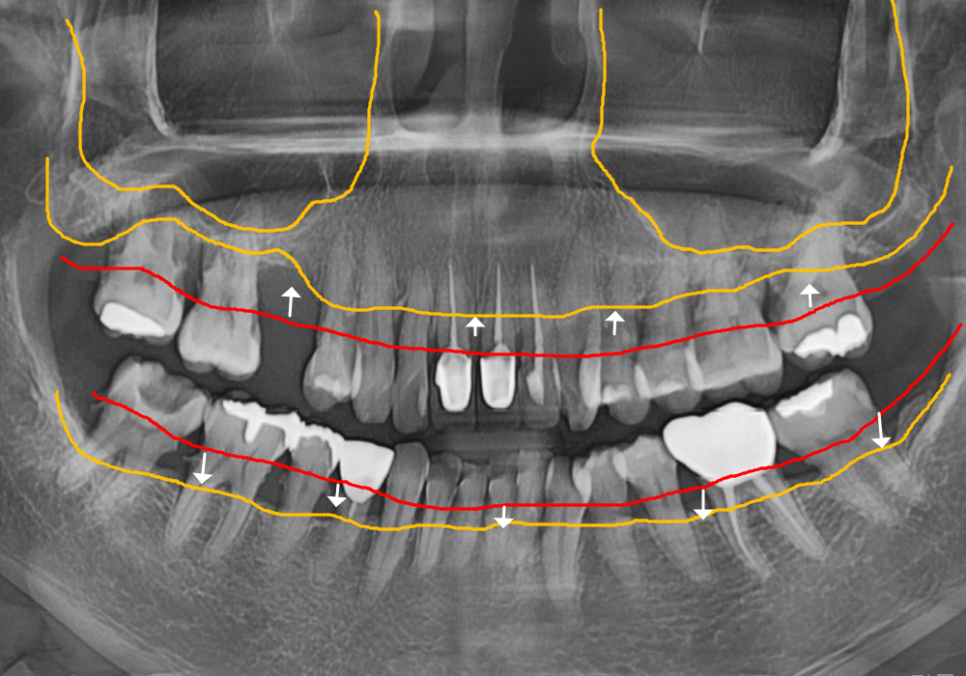

#47 치아: 수직 파절(완전히 쪼개짐)

#47,46,45, #31,32,33, #16,14 : 치아흔들림

전체적인 상태: 잇몸뼈가 녹아

치조골 수평이 매우 낮아진 상태

치료 계획

단순히 치아 하나를 치료해서

될 상황이 아니었기에,

전체적인 재건 계획을 세워드렸습니다.

1 ) 발치 (#16,14, #37,36,35,34, #41~32)

흔들림이 심해 살릴 수 없는 앞니와

어금니들을 발치했습니다.

위쪽 어금니 부위는 뼈가 너무 부족해서

잇몸뼈 위쪽의 빈 공간인

251201

상악동을 들어 올리고 뼈를 채워 넣는

상악동 거상술을 병행하며

임플란트를 식립했어요.

아래쪽 어금니와 앞니 부위도

광범위한 뼈이식과 함께 임플란트를

식립했습니다.